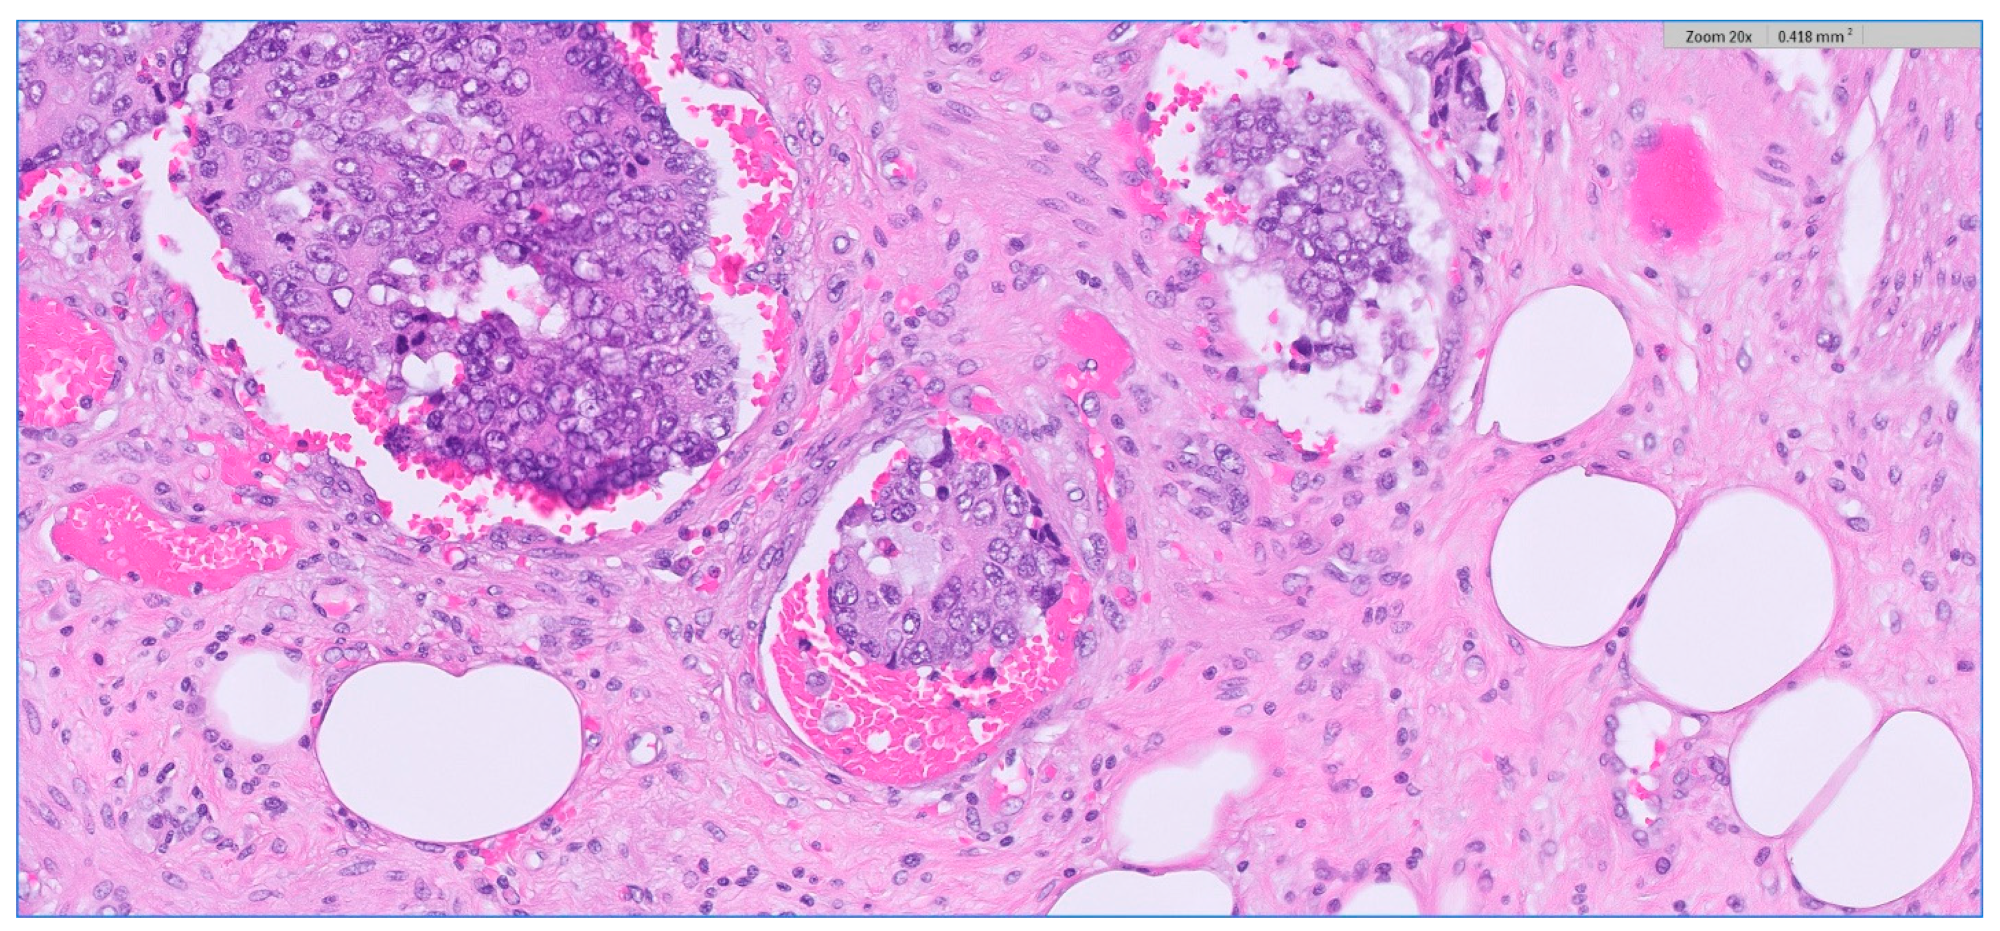

We analyzed the correlation between adjuvant chemotherapy treatment and histopathology bulletin results by using the Pearson correlation coefficient and applying the two-tailed significance t-test. The correlation between adjuvant chemotherapy and a pathological T staging greater than 2 (y)pT > 2 (Figure 6) and between adjuvant chemotherapy and a positive pathological N staging (y)pN > 0 was tested. Other risk factors from the histopathology report that were taken into account were the presence of lymphovascular invasion LVI+ (Figure 7), the presence of perineural invasion PNI+ (Figure 8), positive resection margins Postop+, or a histopathological grade greater than 1 Grade > 1.

Analyzing the relationship between adjuvant chemotherapy, the presence of lymphovascular invasion, the presence of perineural invasion, the tumor grade, and the postoperative resection margins, the results show a very weak positive correlation between them, with a statistically significant p only in the case of the correlation between adjuvant chemotherapy and the presence of perineural invasion p = 0.01 (Table 4). In the case of lymphovascular invasion, positive resection margins, and histopathological grade greater than 1, the correlation with adjuvant treatment was very weak and statistical significance did not exist.

Figure 8. Depiction of perineural invasion; rectal adenocarcinoma. HE stain × 5 magnification.